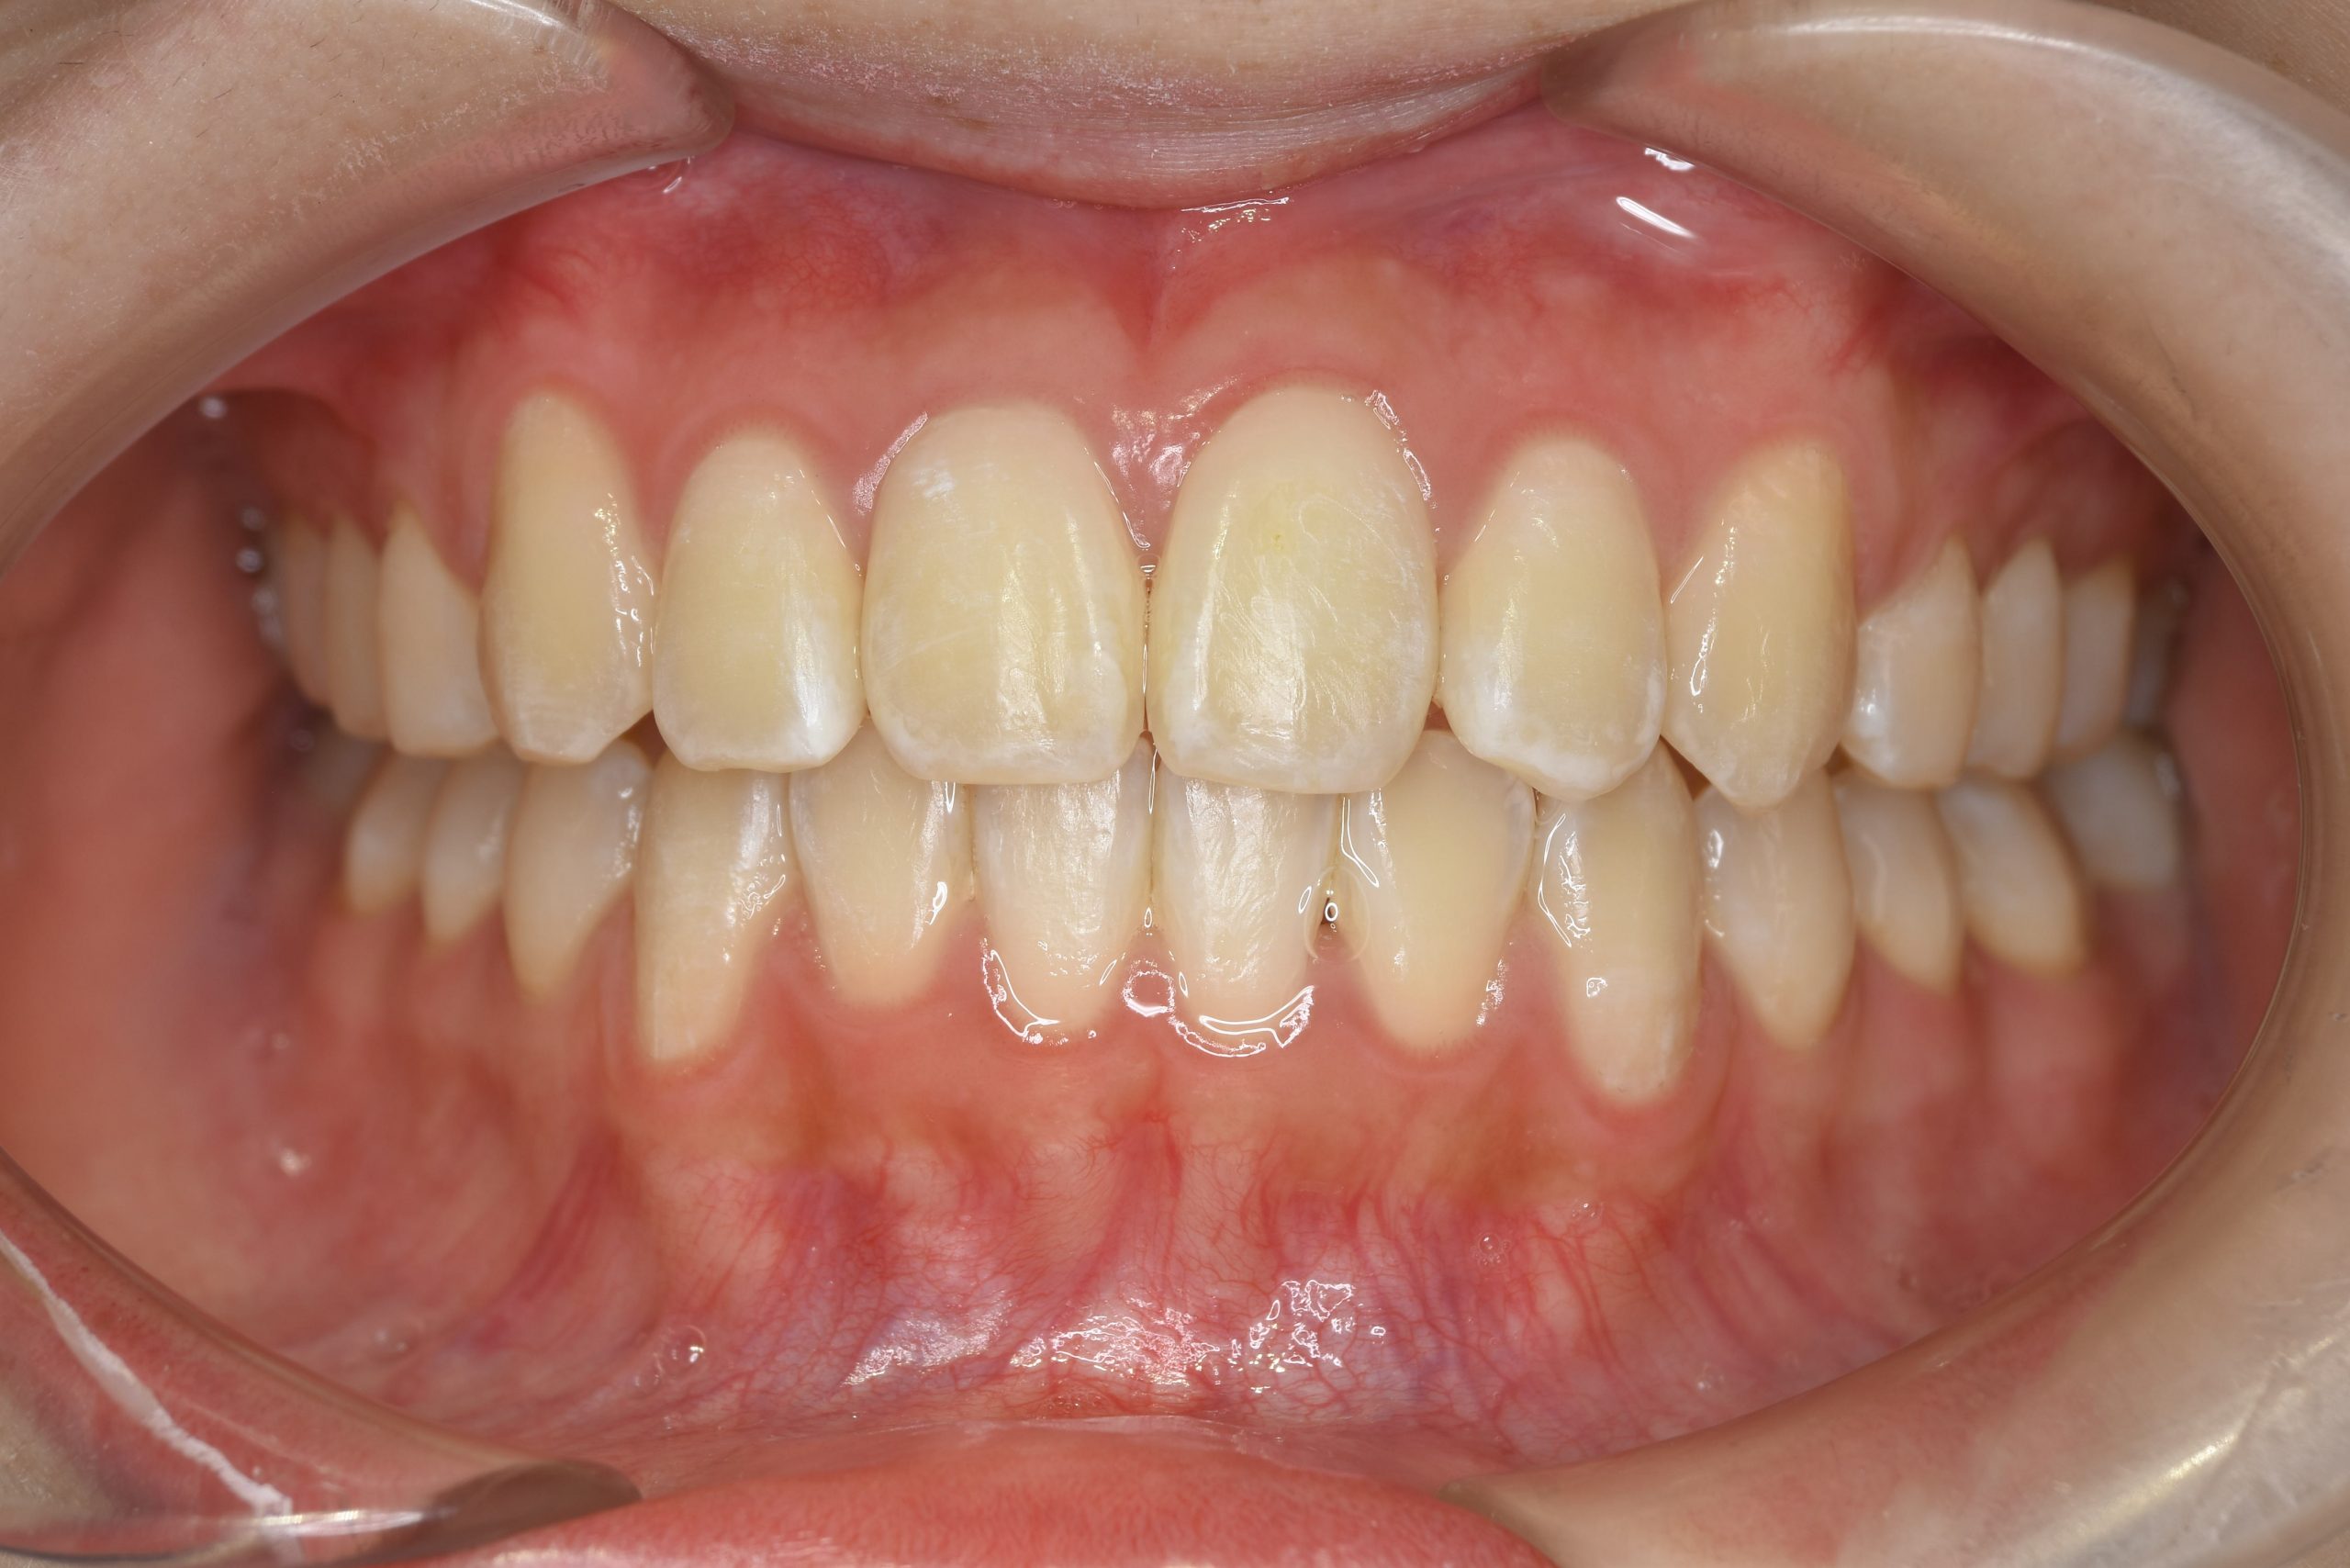

アフター

全顎ワイヤー矯正 症例_815

主訴 前歯の出っ歯|八重歯|下の歯のデコボコ|検診で噛み合わせが悪いと指摘されたこと

施術内容 成人矯正1期治療

治癒期間 1年4か月間

費用 954,800円(税込)